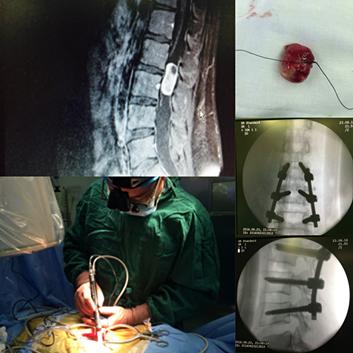

患者才25岁,不能让他就此卧床!经过反复的讨论,结合病理穿刺活检、骨髓穿刺涂片结果,同时完善各项检查,并进行远程会诊(利用电子邮件、网站、信件、电话、传真等现代化通讯工具,为患者完成病历分析、病情诊断,进一步确定治疗方案的治疗方式)。罗湖中医院脊柱骨科医护团队决定为患者实施手术治疗。

特邀省外著名专家及其团队为患者远程会诊

专家团队成员特赴深圳协助手术

罗湖中医院脊柱骨科陈晓东主任师从林建华教授,林教授是中华骨科骨肿瘤学组现任组长,陈晓东代表罗湖中医院脊柱骨科特请福建医科大学第一附属医院林建华教授团队进行会诊,经会诊讨论,初步制定手术方案后,林建华团队朱夏主任特赴深圳协助此次手术。

经术中探查发现,患者右侧股骨出现颈旁类肿瘤组织,医护人员遂为患者行术中冰冻病检,检查提示小圆细胞瘤,淋巴、血液来源可能。

由于患者的病灶局限于股骨颈及股骨近端,专家决定为患者实施双动头人工股骨头肿瘤假体置换,而非全髋关节置换,这样做的意义是保留髋臼的软骨组织,因为软骨是骨肿瘤突破的天然屏障,保留软骨以阻断肿瘤细胞向髋臼侵犯。

手术的过程中,专家提取大量骨肿瘤组织,再次进行病理活检,检查结果提示为非霍奇金淋巴瘤、弥漫性大B细胞淋巴瘤。手术治疗后,医护人员对患者进行基因筛查,寻找靶向药物治疗,后期进一步综合治疗。